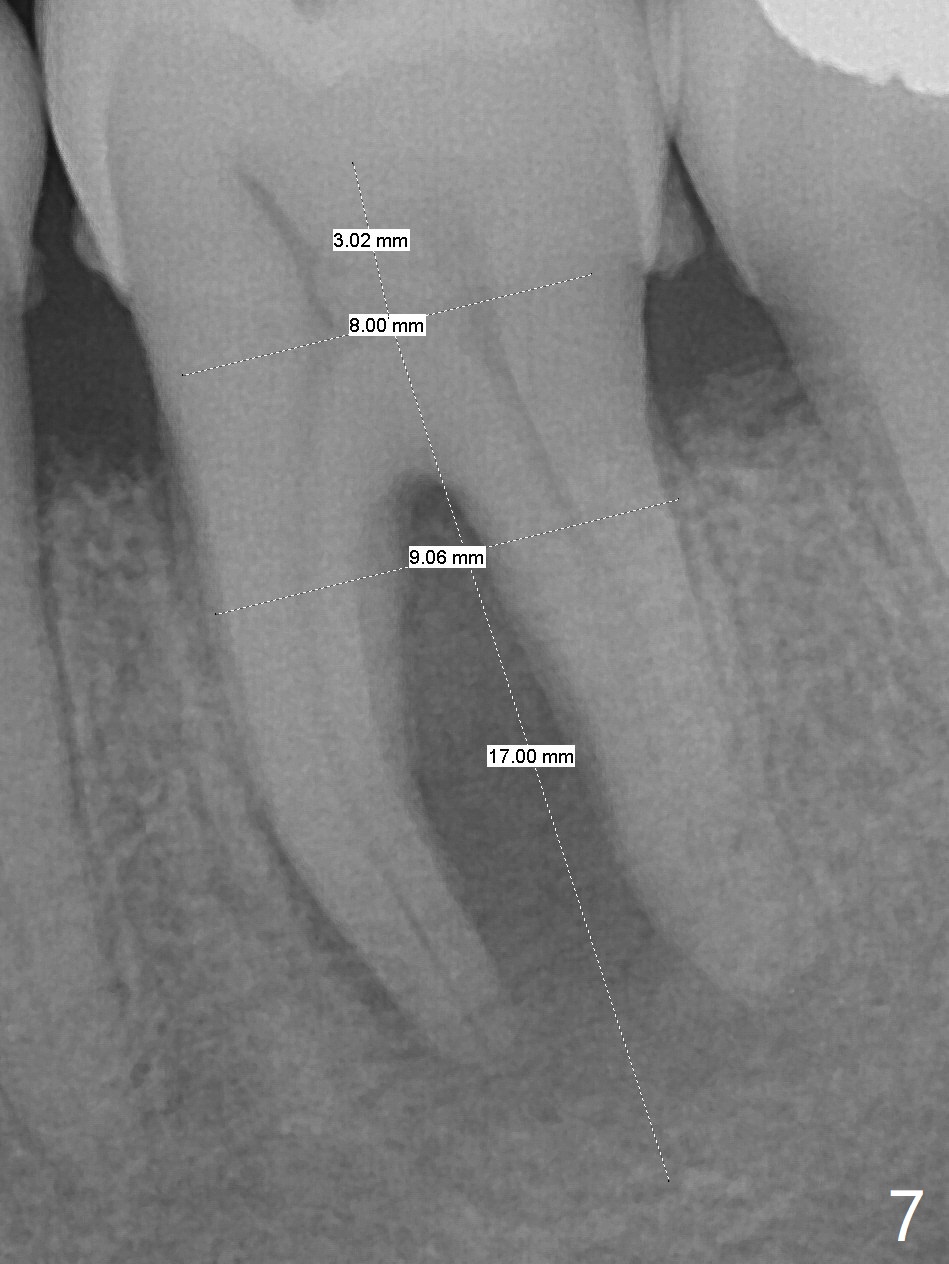

A 62-year-old man (smoker, 1.5 packs a day) has had no dental visit for 12.5 years (Fig.1). His chief complaint is pain at #19 after eating popcorn. The septal bone resorbes (Fig.2,3 *) with granulation tissue between the mesial and distal roots (Fig.4,5 *). Although there is no bony wall defect, the socket is single and large (9x9 mm, Fig.7). The largest (8 mm) cylindrical implant should not be able to obtain primary stability. The biggest challenge for immediate implant is ambiguous the Inferior Alveolar Canal (Fig.1,3 red dashed line). If there were no financial or time issue for immediate implant, CBCT should have been taken. Socket preservation is done instead with Vanilla graft, Human Amniotic Chorion Allograft (membrane) and Osteogen Plug (Fig.6). If he returns for SRP and implant, perform flapless bone expansion for osteotomy. When the patient returns 14 d postop, #19 socket is healing and filled with bone graft (Fig.8 (panoramic X-ray)). When he returns 14 months postop, the socket heals (Fig.9, as compared to Fig.6).